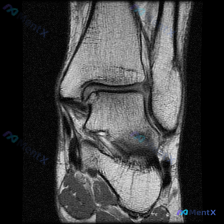

看到这张膝关节MRI读片的需求,问题是观察到「软骨异常」,我整理了一下完整的病例资料和分析思路,和大家分享讨论。 一、影像基本信息 这是一张膝关节矢状位T1加权MRI影像,图像对比度尚可,解剖结构清晰,无明显运动伪影,层面接近膝关节中间矢状面,完整显示股骨远端、髌骨、膝关节间隙及胫骨近端结构。 二、...

今天看到这个挺有讨论价值的读片问题,整理了完整信息和分析思路分享给大家。 病例/影像基本信息 这是一张膝关节轴位T1加权MRI图像,临床提出的问题是评估是否存在软骨异常。 我们先看这份影像的客观观察结果: 1. 整体解剖结构:髌骨、股骨远端滑车轮廓清晰,皮质骨光滑,无骨质破坏或骨皮质中断,骨髓信号大...